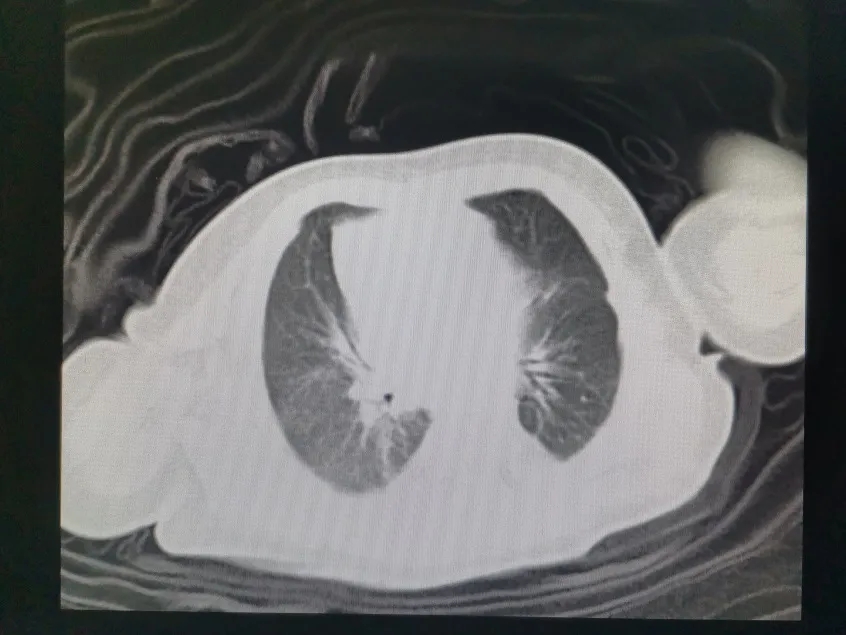

术后CT

由于术后可能出现肺发育不良、气胸、胸腔积液、感染、腹胀等重症,随时都有可能危及患儿生命而致功亏一篑。手术成功不是终点,先天性膈疝术后的管理环节亦非常重要。术后患儿转回新生儿重症监护室,继续给予心电监护及呼吸机支持治疗,胸外科团队术后积极协助指导手术切口护理、引流管的引流排气护理等。在医护团队的悉心照料下,患儿病情平稳,逐步停氧,胸片复查显示膈疝已消失。经过25天的住院治疗,宝宝终于康复出院。